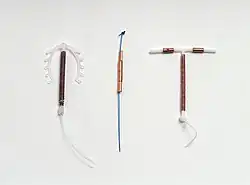

Photo of a common IUD (Paragard T 380A) | |

Device description

There are various of models of copper IUDs available around the world. Most copper devices consist of a plastic (polyethylene) core that is wrapped in a copper wire.[10] Many of the devices have a T-shape similar to the hormonal IUD. However, there are "frameless" copper IUDs available as well, the most popular of which is marketed as GyneFix. Early copper IUDs had copper around only the vertical stem, but more recent models have copper sleeves wrapped around the horizontal arms as well, increasing copper surface area and thereby effectiveness.[37][38]

Frameless IUDs

The frameless IUD eliminates the use of the frame that gives conventional IUDs their signature T-shape. This change in design was made to reduce discomfort and expulsion risk associated with prior IUDs; without a solid frame, the frameless IUD should mold to the shape of the uterus. It may reduce expulsion and discontinuation rates compared to framed copper IUDs.[41]

Gynefix is the only frameless IUD brand currently available. It consists of hollow copper tubes on a polypropylene thread. It is inserted through the cervix with a special applicator that anchors the thread to the fundus (top) of the uterus; the thread is then cut with a tail hanging outside of the cervix, similar to framed IUDs, or looped back into the cervical canal for patient comfort. When this tail is pulled, the anchor is released and the device can be removed. This requires more force than removing a T-shaped IUD, but results in comparable discomfort at the time of removal.[42]